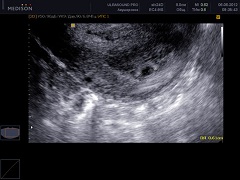

Если происходит имплантация плодного яйца в стенку матки, желтое тело сохраняется до того момента, пока его функцию не возьмет на себя сформировавшаяся плацента. В том случае, если имплантация не происходит, через 10 – 12 дней оно подвергается обратному развитию и исчезает, превращаясь в беловатое тело. Проведение УЗИ на 3 неделе беременности позволяет увидеть в одном из яичников желтое тело.

При проведении УЗИ на 3 неделе беременности в полости матки можно обнаружить плодное яйцо на стадии имплантации в ее стенку. Размер плода на 3 неделе беременности совсем небольшой, поэтому более информативным будет проведение УЗИ на аппарате экспертного класса.